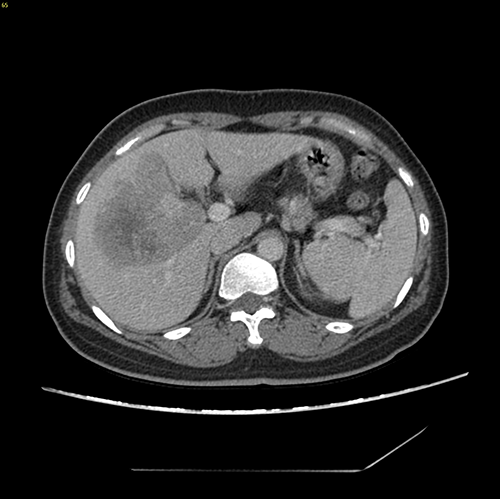

右肝癌----S567切除